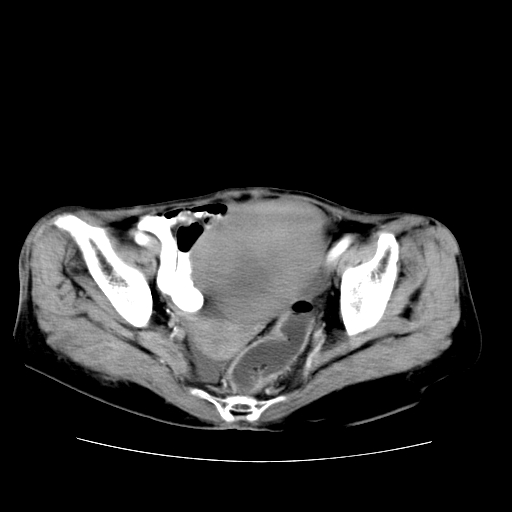

女性,72岁。

主诉下腹部坠痛不适1年余。

子宫增大如孕3月大小,质软,活动可,无压痛。

b超提示:盆腔(子宫前方)低回声团块。

临床诊断:盆腔肿块查。

1、这个肿瘤密度均匀,增强后轻中度均匀性强化,与左侧附件关系密切,肿瘤边缘光整、清晰。

2、左侧卵巢增大呈8×8×10cm大小,实性,表面光滑,边清,左侧输卵管爬行于左卵巢上,子宫萎缩。右输卵管、卵巢萎缩。

3、病理号:092658

左侧卵巢纤维瘤(性索间质肿瘤)

卵巢纤维瘤为良性卵巢性索间质肿瘤,常为单侧发病,当合并腹水或胸腹水时称麦格斯(meigs)综合征,肿瘤切除后胸腹水可消失。ct表现为盆腔内边界清楚的圆形或椭圆形肿块,常有分叶或不规则;肿瘤多为实性,少数为囊性、囊实性,完全囊性者可见壁结节。实性部分与子宫等密度;增强扫描常为轻度强化或几乎不强化。